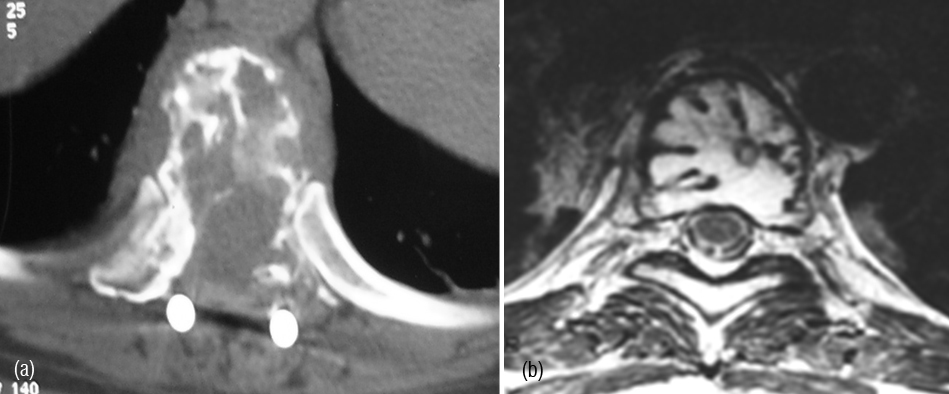

CT and MRI demonstrate lytic areas with struts of bone interspersed. In MRI, plasmacytoma shows a classical minibrain appearance (Figure 4abc). At times, it is difficult to differentiate hemangioma from plasmacytoma (Figure 5ab). It may remain localized for many years but more than 30% progress quite rapidly to generalized myelomatosis with a latent interval of 5-10 years. Radiological features are listed in table 1.

Figure 5: (a) CT (post op.), (b) MRI – Minibrain appearance